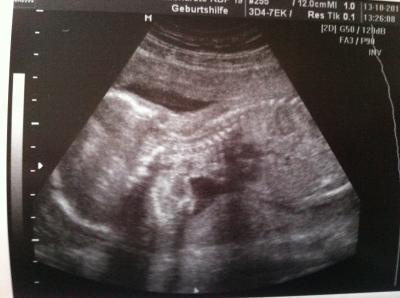

war heute wieder bei meiner FÄ und alles ist super! meiner kleinen gehts sehr gut, alles da wos hin muss und endlich wieder ein bild bekommen..nur leider hat sie sich nicht von vorne zeigen lassen...

Bild zu neues babybild und bauchbild - Forum für Februar - Mamis